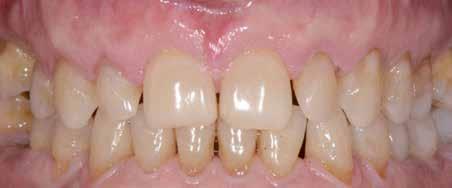

A felnőtt páciensek kezelése során általában egyszerre több ellátásra szoruló elváltozást is diagnosztizálhatunk: hiányzó fogak, kopott fogazat, esetleg régi, nem megfelelő, sérült fogpótlások, rendellenes helyzetben lévő fogak stb… Ezen páciensek kezelésekkel kapcsolatos kérései mindig az esztétikai vagy a rágással kapcsolatos kívánságaik kielégítését szolgálja. A kezelések során a fogorvosoknak nem csak a páciensek kéréseinek teljesítésére, hanem ezzel egyidejűleg a fogazat általános megjelenésének és funkciójának lehetőség szerinti javítására is törekedniük kell. Mindemellett a lehető legtöbb saját foganyag megőrzését és az évek során elvesztett kemény- és lágyrészek pótlását (pl.: hiányzó fogak, sorvadt állcsontgerinc, lágyszöveti defektusok) is szem előtt kell tartaniuk, úgy, hogy közben egy hosszú távon fenntartható eredményekkel járó kezelési tervet állítanak össze. Ezek mindig összetett esetek. Annak érdekében, hogy a fentiekben megfogalmazott összes kezelési célt teljesíteni tudjuk, interdiszciplináris megközelítésre van szükség. Az ilyen komplex rehabilitációs kezeléseket „fogászati megfiatalításnak” nevezzük. Ezeknek a beavatkozásoknak lényege az elhasználódott fogazat biológiai szempontokat figyelembe vevő minimál invazív módon történő helyreállításában rejlik, mely folyamat végére a páciensek fogai visszanyerhetik fiatalkori megjelenésüket.

A rehabilitációs kezeléseknek a célja, hogy a páciensek a lehető leghosszabb időn keresztül képesek legyenek mosolyogni és rágni. A protetikai kezeléseket végző fogorvosoknak helyre kell tudni állítaniuk a fogívek szabályos lefutását és az alsó és felső fogív között megfelelő interokkluzális érintkezéseket kell létrehozniuk. Így lehet csak az ellátás befejezését követően elért végeredmény biológiai szempontokat figyelembe vevő esztétikáját, funkcionális megfelelőségét, hosszú távú fenntarthatóságát biztosítani.

A fogszabályzó kezelések egyik legfontosabb célja, hogy elérjük a lehető legharmonikusabb interokkluzális fogérintkezéseket, továbbá az állcsont relációs helyzetének frontális és szaggitális síkban is megfelelőnek kell lennie. A fogszabályzás befejezésekor a fogpozícióknak nem orthodonciai, hanem protetikai szempontok szerint kell ideálisnak lenniük. Az Invisalign ClinCheck szoftver (Align Technology) segítségével a protetikus az orthodontussal együtt meg tudja határozni azokat a végső fogpozíciókat, amelyek a lehető legjobb végeredmény biztosításához elengedhetetlenek. Bizonyos klinikai paramétereket, mint a fogak klinikai koronájának nagyságát, az egyes fogak fogíven belüli optimális pozícióját, a fogívek egymáshoz viszonyított helyzetét, a fogak között látható rések nagyságát, a frontfogak tengelyének dőlését, az overjet és overbite mértékét már a kezelések megkezdése előtt pontosan definiálni kell. Ezeket az adatokat viszont csak a tervezett végleges fogpótlás ismeretében lehet meghatározni, ezért van szükség az orthodontus és a protetikus szoros együttműködésére.